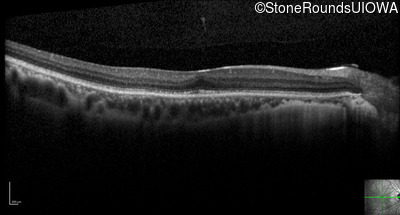

Optical Coherence Tomography - Right - 20/25

Exemplar / OCT Stack

Optical Coherence Tomography - Left - 20/25